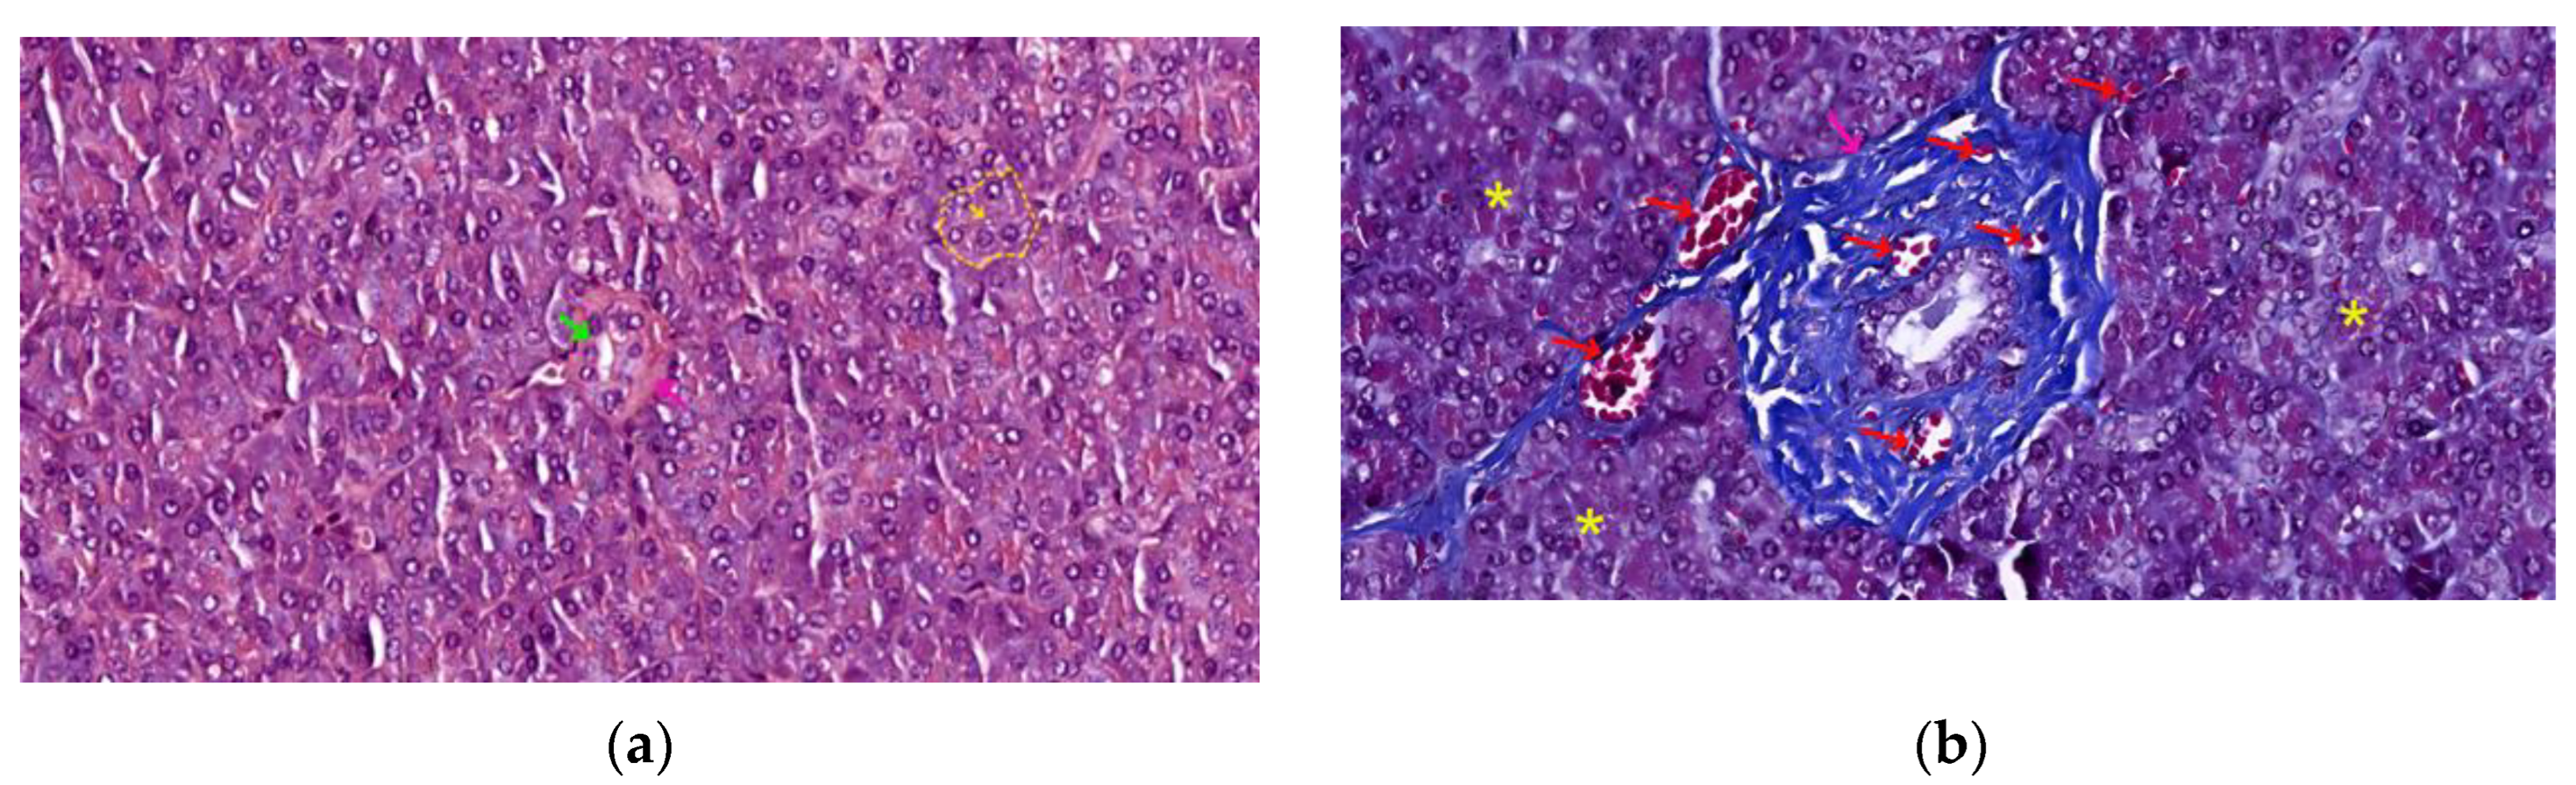

The Exocrine Pancreas

- Centro-acinar cells - delimiting the lumen together with acinar cells; they are small, flattened or cuboidal in shape; the cytoplasm is pale, and the nucleus is oval; these cells are considered reserve cells for acinar and ductal cells (see Figure 4a);

- Intra-lobular ducts - represented by intercalated ducts that continue the lumen of the acini and are delimited by simple cuboidal epithelium; intercalated ducts fuse to form proper intra-lobular ducts, which are larger and delimited by simple cuboidal or columnar epithelium; around these ducts, a loose connective stroma can be observed, with numerous reticulin fibers, yet quantitatively reduced overall; unlike major salivary glands, the exocrine pancreas does not have striated ducts (see Figure 4a/4b);